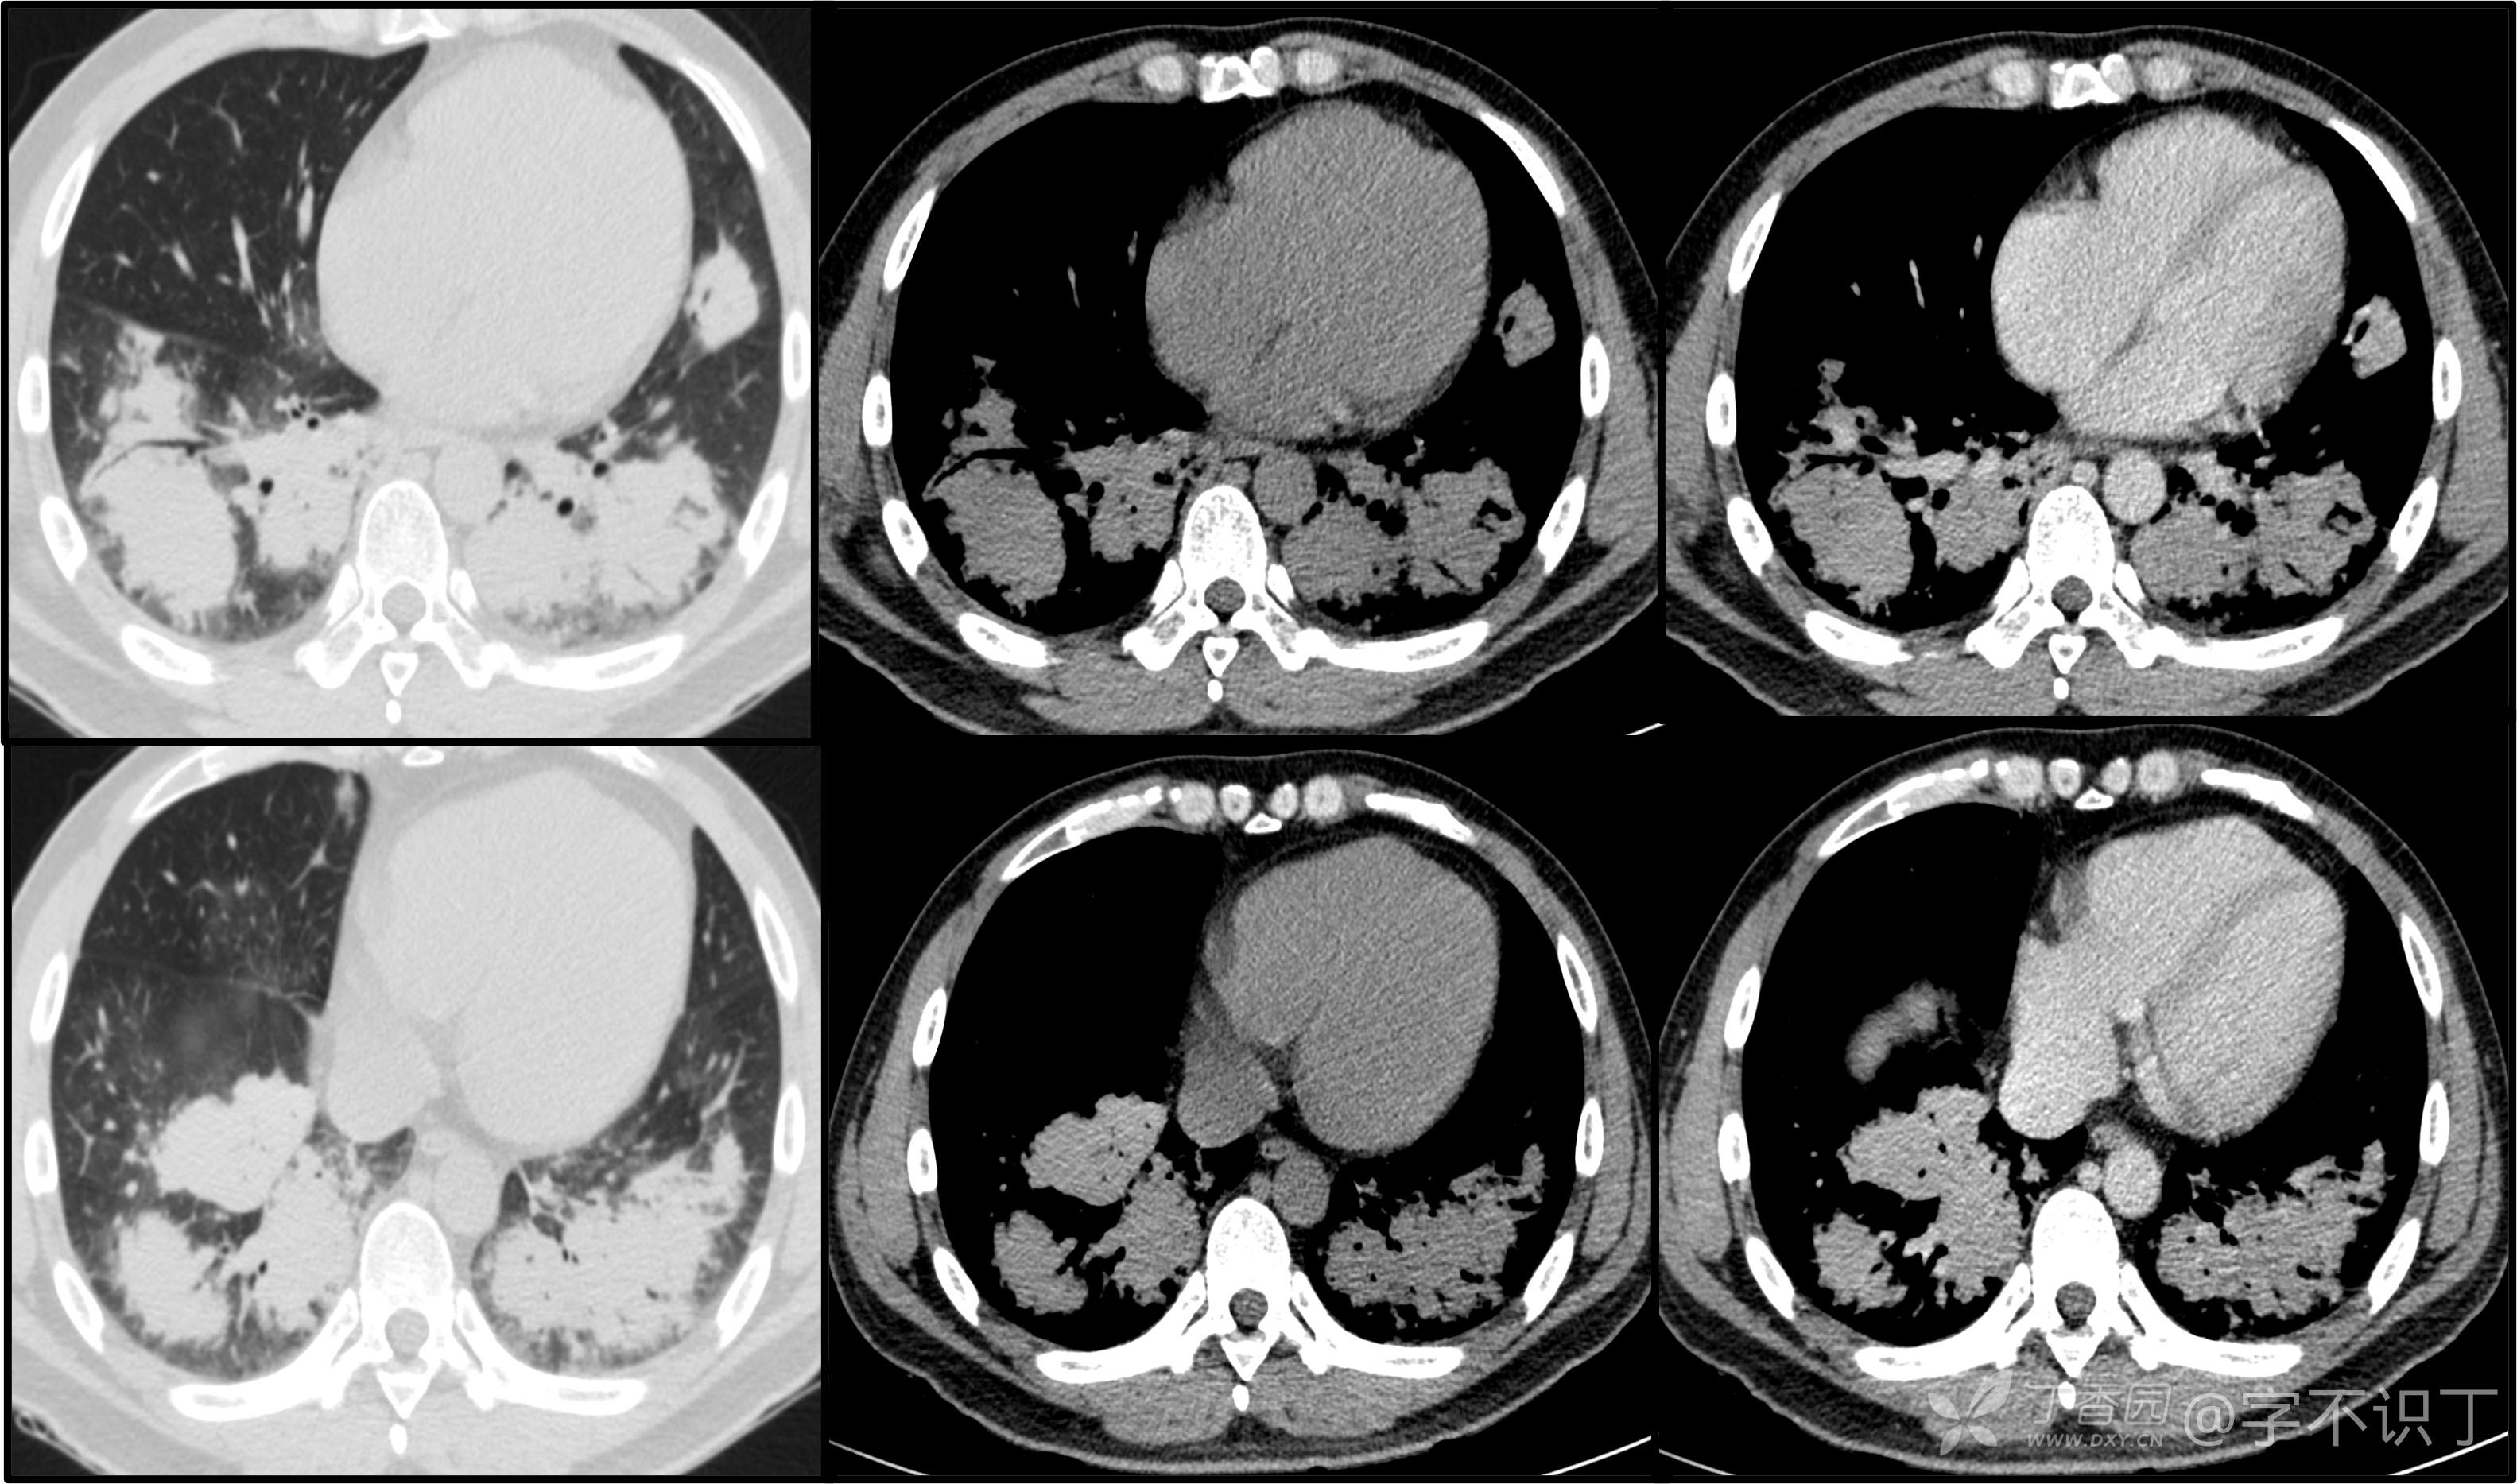

胸部病例讨论

患者性别:男

患者年龄:40岁

主诉:反复咳嗽2年,再发2月,咯血发热5天

简要病史:2年前无明显诱因出现阵发性干咳;2月前咳嗽症状较前加重,有少量白色粘液样痰,未经特殊处理,7天前咳嗽症状较前加重,伴咳黄脓样痰,痰中带血丝,予以哌拉西林舒巴坦+莫西沙星抗感染及祛痰等对症支持治疗,未觉好转,予以拉氧头孢、左氧氟沙星、布洛芬、氨溴索等对症处理,咳嗽、咳痰症状未缓解,仍有发热

体格检查:曾从事装修等工作,近半年从事煤矿管理工作。近期饮酒较频繁。既往有冶游史。

辅助检查:血液病原菌培养、分枝杆菌涂片检查、真菌涂片检查、一般细菌涂片检查、痰培养均阴性